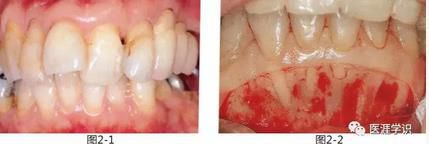

圖2-1,2 為了采集自體骨而將下頜骨頦部進(jìn)行剝離,發(fā)現(xiàn)下頜前牙部無(wú)唇側(cè)骨壁。